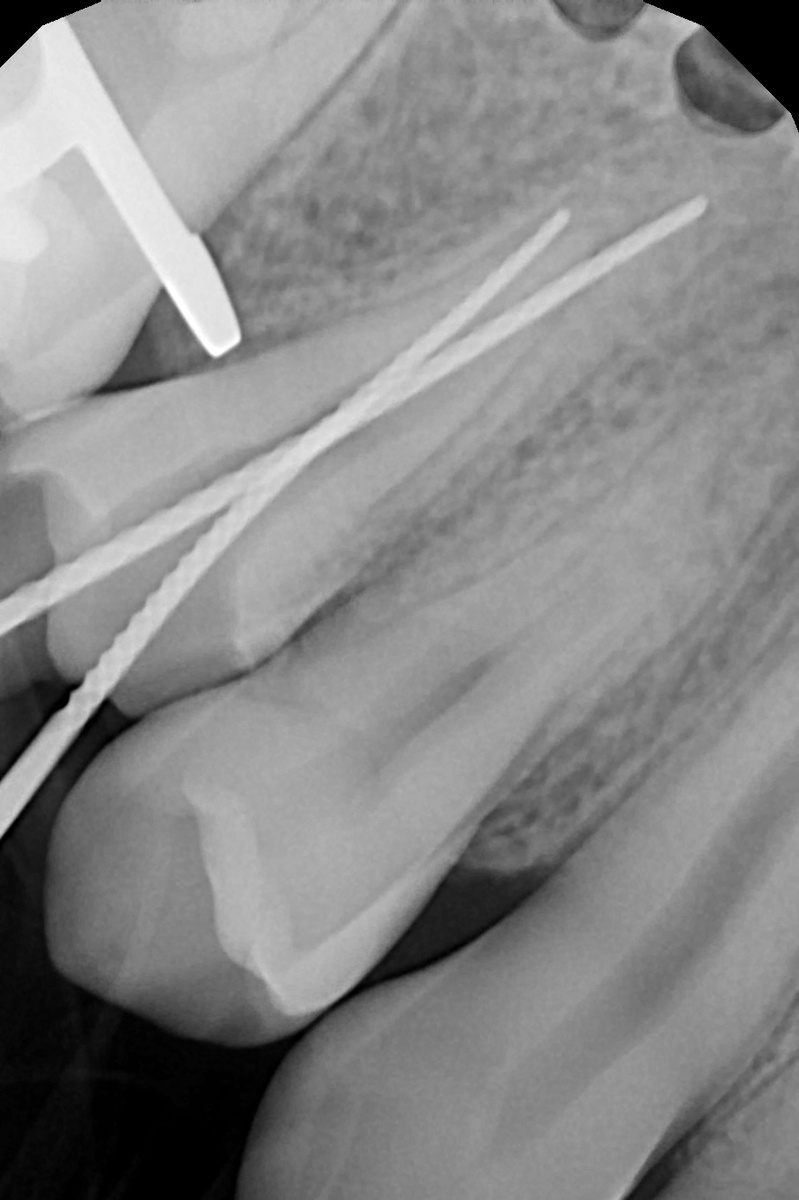

На этой неделе был случай, который люблю и боюсь одновременно. Пациент пришёл с проблемой. Зуб под коронкой. Коронка дорогая, свежая - снимать жалко и нецелесообразно. Но каналы нужно перелечивать. Задача: попасть в каналы через отверстие размером около 2 миллиметров. Не сломать коронку. Не промахнуться. Без микроскопа - это либо удача, либо риск. С микроскопом совсем другой разговор. Микроскоп даёт увеличение до 25 крат. Ты видишь устья каналов, трещины, перфорации - то, что невооружённым глазом просто не существует. Инструмент идёт туда, куда нужно. Не приблизительно, а точно. Я убеждена: лечение каналов без микроскопа - это работа вслепую. Даже у опытного врача. Даже на «простом» зубе. Каналы бывают изогнутые, разветвлённые, кальцифицированные. Это не видно на глаз. Коронку сохранили. Каналы запломбированы. Пациент ушёл с зубом.

Задача: попасть в каналы через отверстие размером около 2 миллиметров. Не сломать коронку. Не промахнуться.

Микроскоп даёт увеличение до 25 крат. Ты видишь устья каналов, трещины, перфорации - то, что невооружённым глазом просто не существует. Инструмент идёт туда, куда нужно. Не приблизительно, а точно.

Коронку сохранили. Каналы запломбированы. Пациент ушёл с зубом.